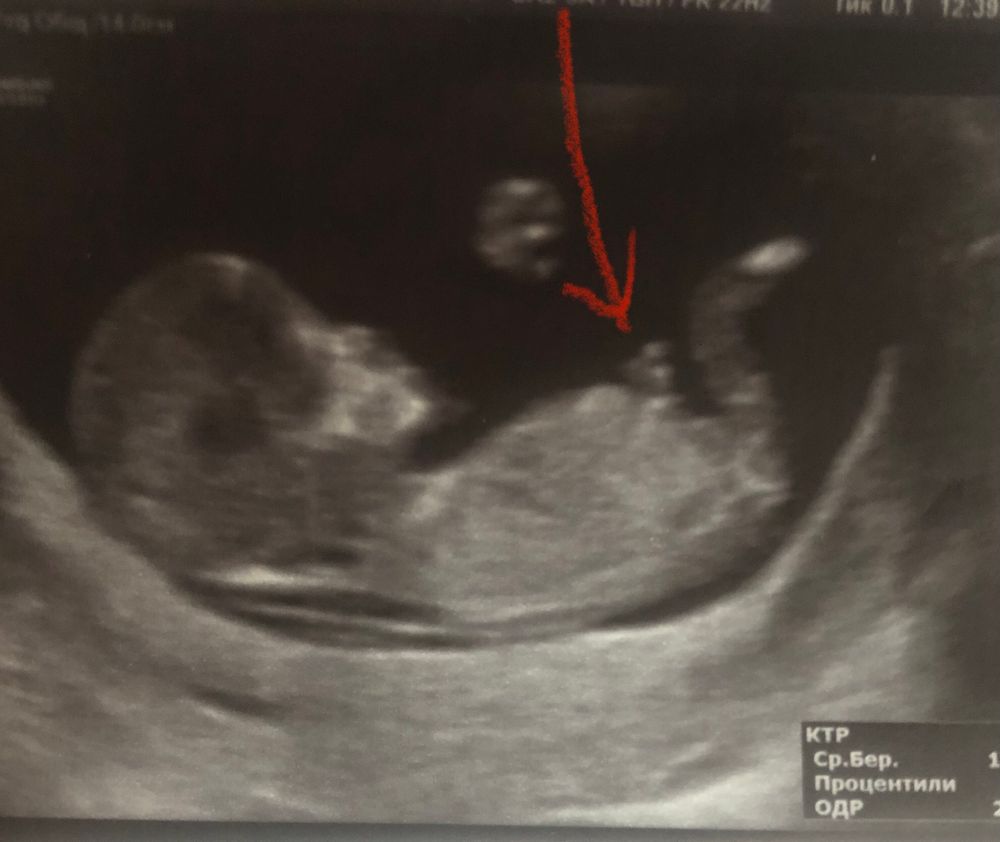

на фото 13 недель срок) стрелочкой отметила, думала что это мальчик , но есть мнения что это пуповина или ножка))) а вы как думаете ?)

Не , это не половой бугорок . Это скорее пуповина или правда ножка